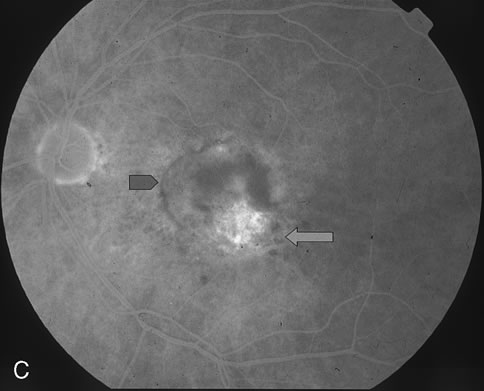

The classic and occult components of CNV are outlined in Figure 2. The percent of the CNV that is classic can then be determined as a proportion of the total CNV. In Figure 2A and B, the area of classic CNV measures 978 square microns and the total lesion measures 11,180 square microns. The classic component is thus 9% of the entire CNV and this lesion is classified as “minimally classic” CNV (defined as less than 50% classic CNV).23,40 The fluorescein angiogram demonstrates another mixed classic and occult CNV lesion in Figure 3. Using digital area measurements, the lesion in Figures 3A and B is composed of 79% classic CNV and fulfils the criteria for predominantly classic, subfoveal CNV that may benefit from verteporfin-PDT based on TAP findings.23,40 The TAP studies also demonstrated a visual benefit in eyes that had prior nonfoveal, thermal laser photocoagulation and subsequent recurrence of CNV below the fovea.23,40 In Figure 4A, subfoveal CNV recurrence in an eye with prior thermal photocoagulation is demonstrated. One month following verteporfin-PDT treatment, Figures 4B (early phase) and 4C (late phase) demonstrate characteristic hypofluorescence of the treated subfoveal CNV on fluorescein angiography.

Fig. 3. A. Fluorescein angiogram reveals predominantly classic CNV. B. Digital imaging outlines the classic component (A) and the entire lesion (classic and occult, marked as B). The area of classic component measures 7,315 square microns. The entire lesion measures 9,302 square microns. The areas marked with an asterisk correspond clinically to drusen. C. Greatest linear dimension (GLD) of the entire classic CNV measures 4,184 microns.